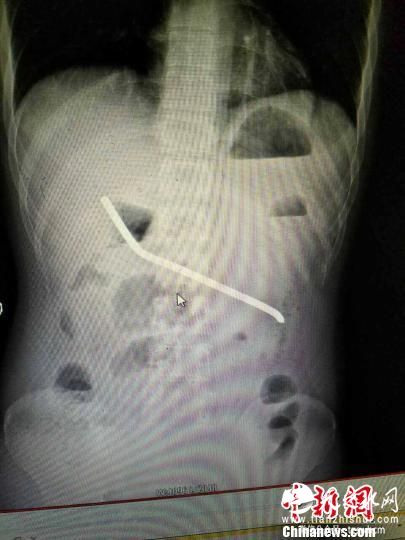

钢筋在男子身体里。刘杰华摄

“医生啊,救救我儿子吧!”6月22日,怀化市第二人民医院靖州医院胃肠外科,突然传来了一阵急促的呼喊声。值班医师李辉上前一看,发现患者昏昏沉沉,浑身热得烫手,腹部肿胀,硬得像块木板。李辉赶紧护送患者至影像科做检查。“没想到,小伙子胃里面竟然有一根长约20厘米的钢筋。”李辉说。

当晚19时,胃肠外科主任医师唐红明及李辉给男子进行了急行剖腹探查术,并在术中发现这根钢筋已经穿出胃壁及胰尾被膜,腹腔有大量的脓肿,形成了脓肿包块。经一个多小时耐心细致的手术,钢筋被取出来了。

唐红明说,因时间过长,钢筋穿破胃壁,形成了大量的腹腔脓肿,加之钢筋已经锈迹斑斑,且靠近脾动脉,如果再迟来医院一天,后果不堪设想。